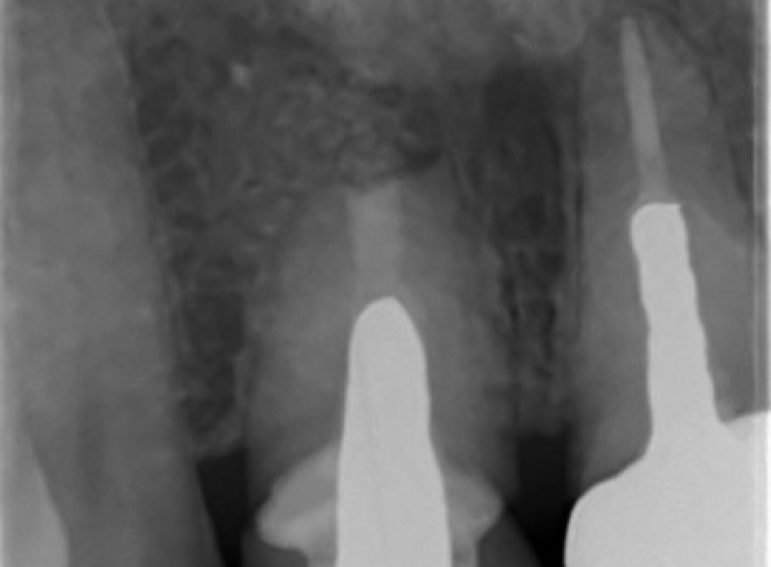

Case 26 – Endodontics

Repeat apicectomy with grafting